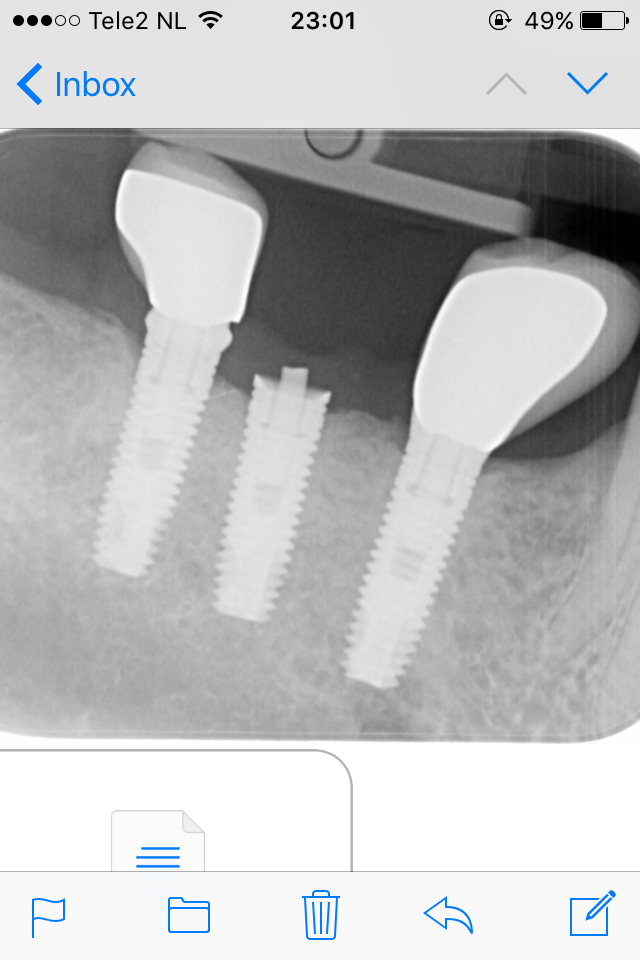

Hace unos dias vino el paciente con la corona en la mano del implante 46. El tornillo se fracturo y conseguimos extraerlo. Necesitamos saber el sistema del implante para encargar [...]